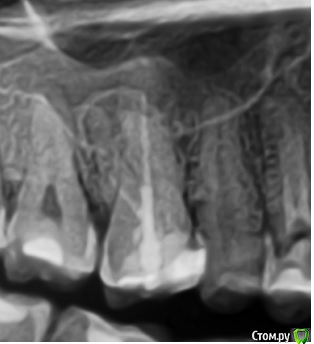

vse32 Опубликовано 6 ноября, 2019 Поделиться Опубликовано 6 ноября, 2019 Я стоматолог терапевт, поэтому вопрос почти как от обывателя.16 зуб, женщина около 35 лет (не видела ее, коллега мужа по работе). В сторонней клинике сделали ОПТГ и КТ и рекомендовали удаление с одномоментной имплантацией. Со слов женщины предложен корейский имплантат за х рублей + подсадка за х рублей. Или американский имплантат за 2х рублей без подсадок.Вопрос - нормально ли это делать одномоментно при наличии кистогранулемы (вне обострения).Лечить эндодонтически могу, но сомневаюсь в гарантийности работы. Ссылка на комментарий

Бендер Опубликовано 7 ноября, 2019 Поделиться Опубликовано 7 ноября, 2019 Кистогранулемы? Ссылка на комментарий